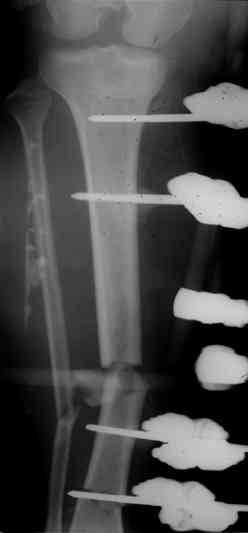

Коллеги! Прошу совета, какую тактику избрать при лечении.Больной 27 лет, мотоциклист. Поступил 23.04.10 ДЗ. О. перелом н.з левого бедра Gustillo 3b (c повреждение бедренной вены), О.Правого бедра Gustillo 2, з. фрагментарный перелом левой голени.При поступлении Hb 66 ISS 40, Фиксация стержневыми аппратами, сосудистые хирурги выполнили шов вены. Выполена резекция бедренной кости 9 см. На 7 сутки Желудочно-кмшечное кроветечение из стрессовых язв, 12 сутки флотирующий тромтоз 14 см установлен кава-фильтр. На 15 сутки закрытие ран местными тканями. Раны заживают первично. Воспаления на стержнях нет. В настоящий момент планируем. Переход со стержневых аппаратов на стержни с антибактериальным покрытием на правом бедре и левой голени. Левое бедро планируем продолжить фиксировать в стержневом аппарате.

Вопрос: что делать с левым бедром? Учитывая внутрисутавной характер перелома, дефект бедра 9 см.

И тракцию бедра на стержне. Типа (СМ картинки).